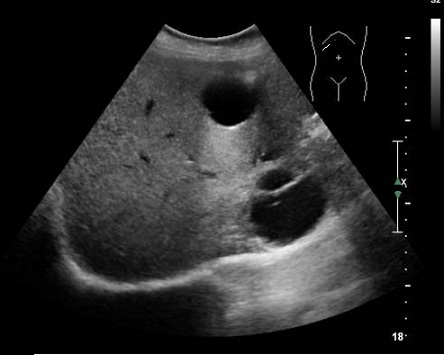

Image TDM de kyste du

foie : Image lesionaire arrondie , de taille variable souvent de

quelque centimetrique . Densite liquidienne de 0

a 15UH

Image radiologique TDM d'une kyste simple

du foie droit en coupe axiale : Aspect

lesionnel a densite variee de 7-15 UH ( hypodense )

avec bord lisse , bien definie et regulier |

Même cas en coupe coronal (

fleche rouge ) . La kyste est situe du foie droit

juste a inferieuse du coupole diapragmatique droit |